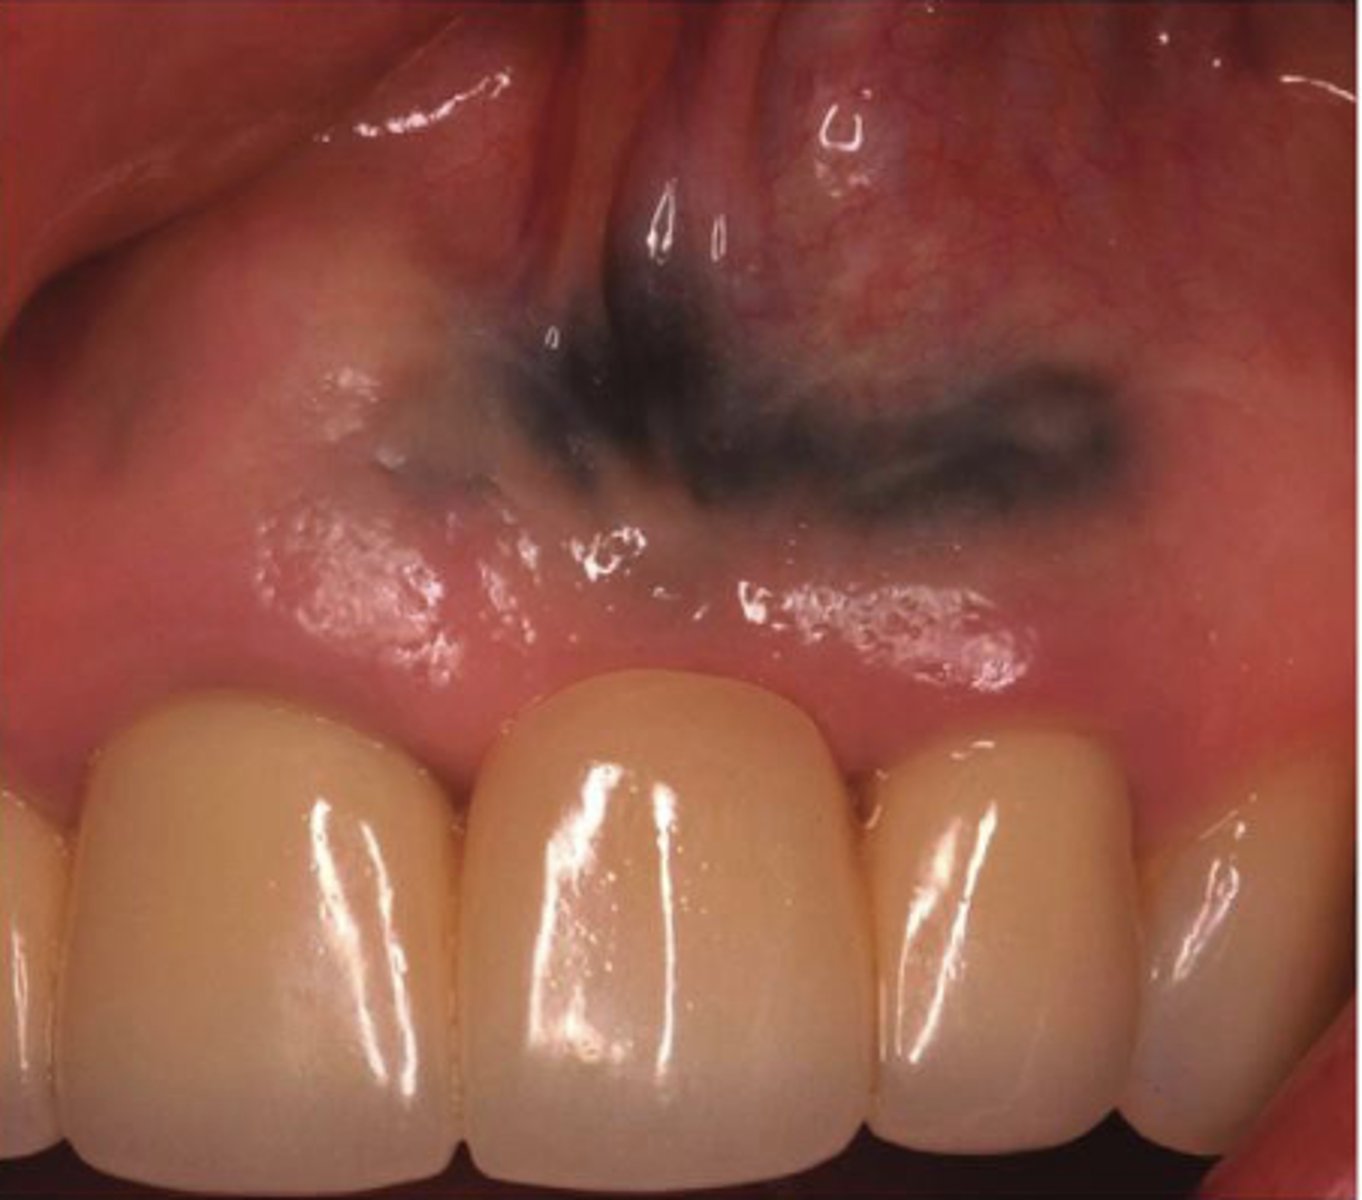

What type of pigmented lesion?

amalgam tattoo

These are clinical features of what?

- Asymptomatic, localized

- Blue-gray macule

- Localized around areas with amalgam restorations

amalgam tattoos

What is the most common location of amalgam tattoos?

gingiva/alveolar ridge mucosa (50%, then buccal mucosa, then floor of mouth)